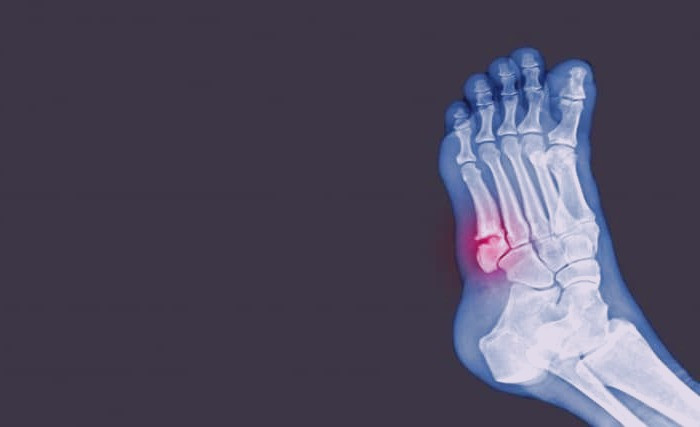

پوکی استخوان باعث می شود که استخوان ها ضعیف و شکننده شوند. این بدان معنی است که استخوان ها به حدی شکننده می شوند که یک افتادن یا یک تنش خفیف مانند خم شدن یا سرفه می تواند باعث شکستگی آنها شود. شکستگی های مرتبط با پوکی استخوان اغلب در لگن، مچ دست یا ستون فقرات رخ می دهد. این موضوع بسیار مهم است که افراد در مورد پوکی استخوان آگاهی داشته باشند و اقدامات پیشگیرانه را انجام دهند تا از بروز چنین مشکلاتی جلوگیری کنند.

• شکستگی استخوان که خیلی راحتتر از حد انتظار، اتفاق افتاد

شکستن آسان استخوان ها از علائمپوکی استخوان